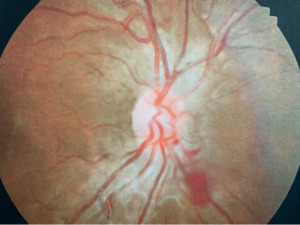

A 21-year-old African American woman presented at Navy bootcamp with complaints of a sudden-onset black spot in her right eye that occurred immediately after vomiting earlier that day. Aside from a complaint of acute gastrointestinal pain, the patient’s medical history was unremarkable. Visual acuity was 20/20 in each eye. Confrontation visual fields were full to finger counting in both eyes. Extraocular muscle and pupil testing were unremarkable. Slit lamp biomicroscopy was remarkable for diffuse brownish corneal epithelial deposits with a central whorl-like pattern in both eyes (Figure 1). Intraocular pressures were right eye 13 mm Hg and left eye 12 mm Hg by noncontact tonometry. Dilated fundus evaluation was remarkable for vessel tortuosity in both eyes and a small vitreous hemorrhage inferior-nasal to the optic disc in the right eye (Figure 2). Posterior segment findings of the optic nerve, macula, and periphery were otherwise normal in both eyes.

Unique to this case is the presentation of vitreous hemorrhage. Vitreous hemorrhages are supplied by the central retinal artery and present within the vitreous anteriorly. The mechanisms for the pathogenesis of vitreous hemorrhage can include retinal vascular disorders with or without associated ischemia, breakthrough vitreous hemorrhage, or rupture of blood vessels (i.e., neovascularization).14 Blood in the vitreous occurs as an inflammatory reaction formed from polymorphonuclear neutrophils that break down fibrin macrophages then phagocytose red blood cells and cellular debris.15 Increased intra-abdominal pressure associated with an absence of valves in the venous system anterior to the heart leads to an increase in intraocular pressure and subsequent rupture of superficial retinal capillaries.12 The presentation of a vitreous hemorrhage in this case was likely due to the patient’s gastrointestinal distress, which is consistent with Fabry disease, and subsequent vomiting/Valsalva maneuver.

There are no documented cases of Fabry disease with Valsalva retinopathy. The Valsalva maneuver, otherwise known as hemorrhagic retinopathy of Valsalva, is the rupture of superficial capillaries secondary to an increase in retinal venous pressure following a sudden change in intrathoracic or intra-abdominal pressure.12 A rapid rise of intraocular venous pressure can cause spontaneous rupture of the superficial retinal capillaries, potentially leading to sudden and painless decrease in visual acuity in an otherwise healthy eye.14 Vessel tortuosity may have also put this patient at increased risk for hemorrhaging owing to weaker vasculature. Depending on the size of the vessel affected, Valsalva retinopathy can vary in presentation. It is largely self-limiting in nature but can require surgical intervention if larger or if resolution is not seen after 3 weeks of observation. In this case, gastrointestinal distress associated with Fabry disease was the presumed cause of this episode of vomiting, and the hemorrhage resolved without treatment.